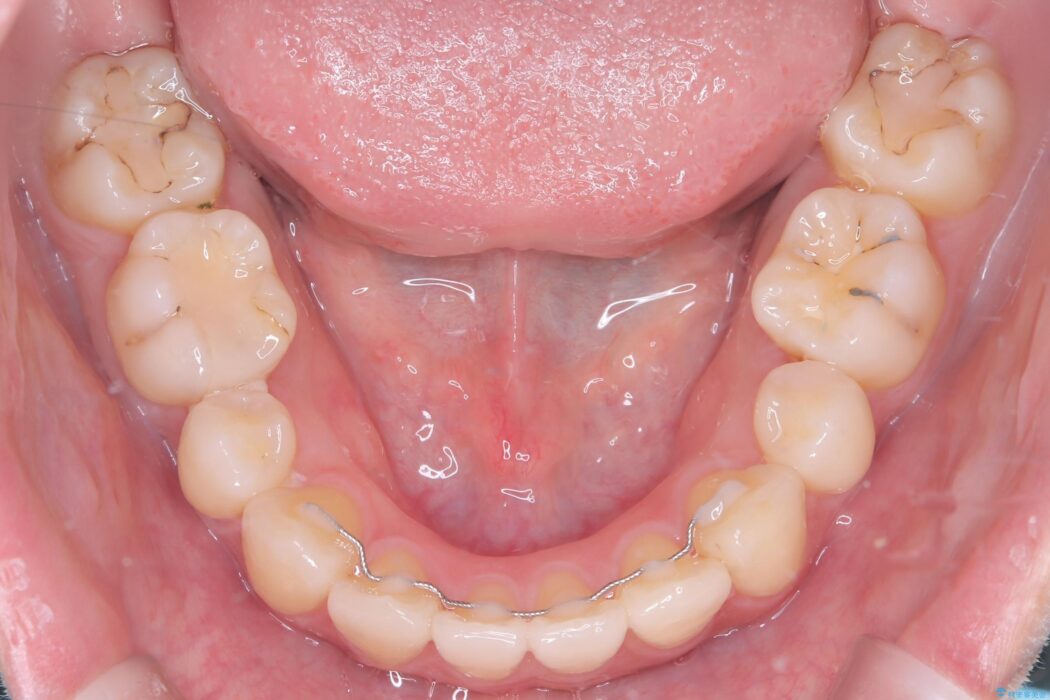

口元が出ていることを気にされ、ご来院された患者様です。

精密検査の結果、前歯を大きく後退させ、口元の突出感を改善するためには、スペースの確保が必要と診断しました。

そこで、上下左右の第一小臼歯(4番目の歯)を計4本抜歯し、そのスペースを利用して前歯全体を奥へ移動させる抜歯矯正の治療計画を立案。

確実な歯の移動を実現するため、ワイヤー矯正装置を使用しました。